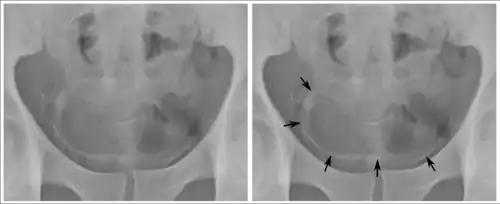

Some forms of medical imaging exist to visualise the bladder. A bladder ultrasound may be conducted to view how much urine is within the bladder, indicating urinary retention. A urinary tract ultrasound, conducted by a more trained operator, may be conducted to view whether there are stones, tumours or sites of obstruction within the bladder and urinary tract. A CT scan may also be ordered.